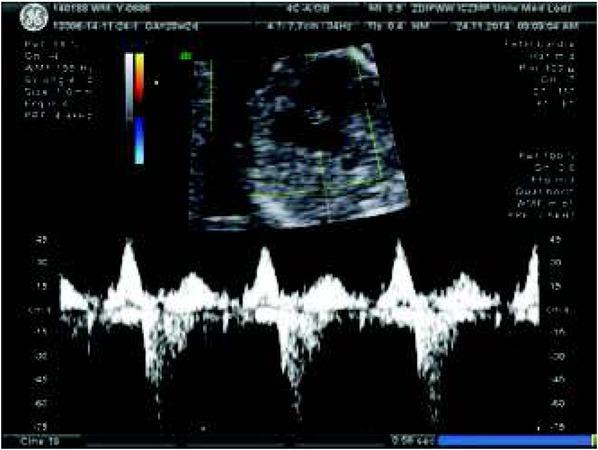

Fig. 1